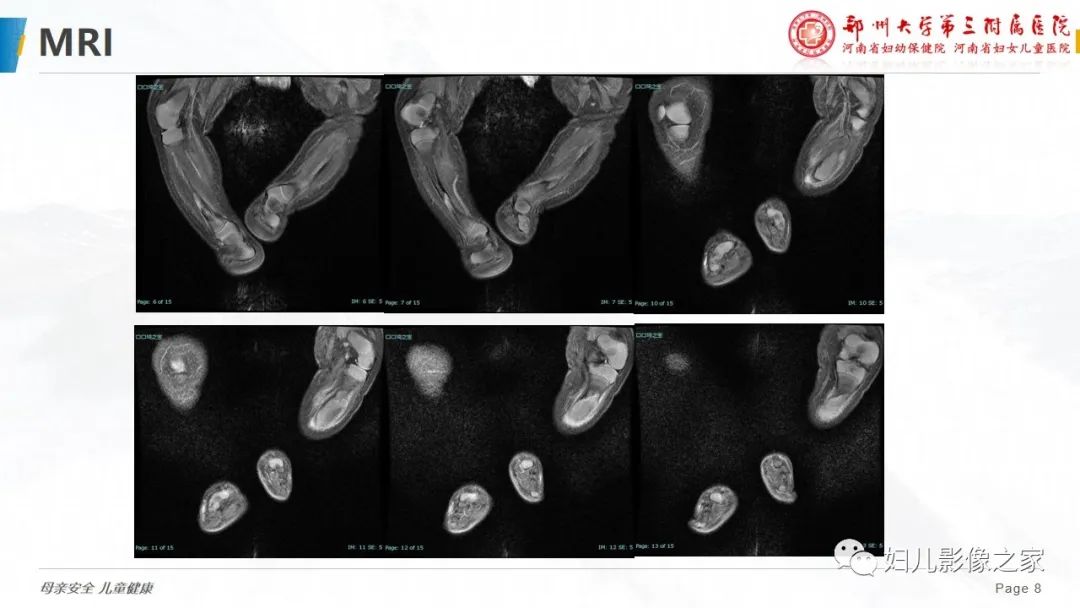

【PPT】骨纤维结构不良-8